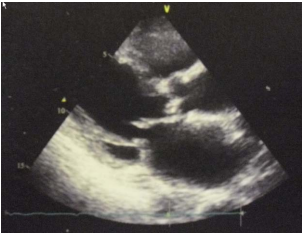

3. 82歲老婦人到院主訴五天來有日趨嚴重的呼吸困難。病史顯示30年前就有醫師告知心臟雜音,因無症狀,未曾有任何治療。近五年來運動耐受逐漸不佳,且偶有突發性悸動及心絞痛,特別在步行樓梯間更加惡化。住院當日清晨3點突然重度呼吸困難,因而急診住院。理學檢查:血壓110/62 mmHg;心跳90/分;頸靜脈怒張。心臟大小正常,但在右上胸骨緣及心尖部有Gr III/VI systolic murmur, S2減輕:其他所見尚無異常。其胸部X光、心臟超音波及心電圖如圖。WBC,5.2 k/micro L;AST,21U/L;CK,111U/L;CK-MB,14.6U/L;Troponin I,0.06 ng/ml。請問下列何項處置最恰當? (A) Percutaneous coronary intervention (B) Aortic valve replacement (C) Nitroglycerin IV infusion at the rate of 15mcg/min (D) Titrate PO carvedilol starting from 3.125 mg and reassess in 3 months (E) Treating with IV digoxin 0.125mg in conjunction with IV bolus Furosemide 20mg and then 20 mg BID

超音波

Estimated aortic valve area = 0.37 cm2 With the peak Ao flow at 580 cm/sec ; the peak pressure gradient at 134mmHg and the LVEF (56%)